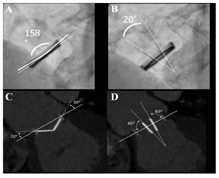

荧光透视成像对于机械性PHV的评价简便、易行且无创,主要用于跨瓣压差异常升高的患者。该技术可正确识别植入瓣膜的类型并评价其功能[39,40,41]。通过合适的投影可评价瓣叶运动、瓣环运动、瓣膜各部位的破裂或移位。瓣环根部异常的倾斜或者摇摆提示广泛的瓣叶开裂。但该检查不能进行血流动力学的评价,也不能提示瓣叶动度减低的原因。

通常情况下,荧光透视成像时患者取仰卧位。在三个主要投影观察PHV:a) 后前位(0°)及侧位(90°)投影来识别瓣膜的"原位"方向;b)"侧位"投影(射线束与瓣环及碟瓣的倾斜轴相平行)有助于计算瓣膜开放和关闭的角度;c)"正面"投影(射线束与瓣膜流出道相平行)仅用于人工二尖瓣的评价。由于手术的人工瓣膜方位不同,常常需要仔细调整患者的体位和采用头-尾向成角的方法进行观察。值得注意的是,在评价主动脉瓣瓣叶动度方面荧光透视成像优于超声心动图。

每一个体位均需记录一动态图像(大约10个心动周期),从中选择图像帧对瓣膜的运动距离进行评价和测量。在人工瓣膜完全开放和完全关闭时两个瓣叶之间的距离为开放角和关闭角(图1A,图1A和图1B)。对于人工单叶碟瓣,开放角定义为瓣膜完全开放时罩与碟瓣间的距离,而对于人工双叶碟瓣,开放角为完全开放时两个碟瓣之间的距离(图1B)。尽管对某些机械性瓣膜X线穿透度较差,但仍经常采用荧光透视成像法进行评价。

心脏CT通常不作为常规检查,主要用于疑似心脏瓣膜功能障碍或其他并发症时。CT可对瓣膜运动、整体性、瓣膜或瓣周病变(如心内膜炎、瘤样扩张或其他周围组织受累)提供额外的诊断信息[43,44]。CT可替代荧光透视成像用于测量机械性PHV的开放/关闭角(图1A,图1C和图1D),以及用于TOE不能明确的生物瓣瓣叶显像(如瓣叶增厚、钙化或血栓形成)[45,46,47,48]。CT可显示瓣叶对合不良,在某些病例可定量测量反流口面积。也有可能识别瓣周反流,这取决于病变的大小及瓣环的荧光透视成像程度[49,50]。动态CT重建时发现瓣环的摇摆运动有助于瓣环开裂的诊断。CT可鉴别血栓形成和血管翳[51,52,53,54,55],并可通过测量解剖瓣口面积(几何学瓣口面积,GOA)来定量人工生物瓣膜的狭窄程度[6]。瓣膜的梗阻性或者反流性功能障碍所导致的形态学改变可表现为心室或心房的扩大或超声增强剂显示的血流淤滞。在再次手术术前准备时,心脏CT可用于评价冠状动脉情况或冠脉桥血管的通畅情况,尤其适用于非退行性瓣膜性心脏病的年轻患者[56,57]。术前CT可估测胸骨及RV之间的距离,有助于避免胸骨切开术时的意外创伤。由于左回旋支紧邻瓣环可能导致损伤(尽管较为少见),可采用冠脉CT血管造影进行评价[58]。

采用心电图同步采集或重建,可在自由呼吸状态下(取决于时间分辨率)在任意切面获取或重建亚毫米级别的均质空间分辨率图像。如果获取的是整个心动周期的数据,则可用于重建连续心脏时相的图像,有助于评价瓣膜结构位移。与实时超声心动图不同的是,动态CT重建仅显示单个心动周期。与荧光透视成像类似,透射线较好的机械性瓣膜动态评价不需要注射造影剂。与冠脉CT血管造影类似,心脏CT可能需要药物控制心率[59]。PHV在瓣膜完全开放或者完全关闭时显示最佳,正常开放角度取决于PHV的类型,有时亦取决于瓣膜植入的位置(表6)[6,50,51,52,60]。右心瓣膜尤其是人工三尖瓣的造影增强显像,常因造影剂由上腔静脉进入心腔的不均质混叠而显示欠佳。这时可以选择在再循环过程中采集图像,或者是在合适的时间、按适当比例从上、下肢血管同时注入造影剂可改善右心造影剂的均质化。